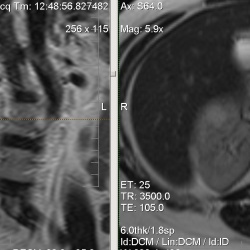

07.06.2014 - 19:29

За счет чего киста такая "неяркая" на обычных Т2 ?